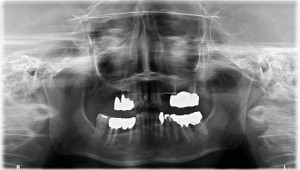

上左右の奥歯を失ってしまったため、保険の入れ歯を入れたが、違和感が強く、しっかり噛むことができないため、インプラントを併用した入れ歯を作ることで違和感なく、しっかり噛むことができるようになった。 また通常の入れ歯は、はずれないようにするため金属のバネを歯に引っ掛けるため見た目も悪いが、インプラントによって固定されているためバネもなく、見た目も非常に良いものとなっている。

術前

術前レントゲン写真